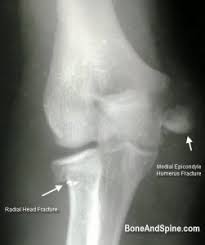

#udayxray #fracturemedialepicondyle #fracturelateralepicondyle #fractureradialhead दोस्तों इस वीडियो में मैंने एल्बो ज्वाइंट के फ्रैक्चर के बारे में बताया है.

The common extensor tendon attaches to the lateral epicondyle, acting as the common attachment for the superficial extensor muscles of the forearm. The lateral epicondyle of the humerus is a large, tuberculated eminence, curved a little forward, and giving attachment to the radial collateral ligament of the elbow joint, and to a tendon common to the origin of the supinator and some of the extensor muscles. Tennis elbow assessment explore the. Related online courses on physioplus. Lateral epicondylitis is defined as a pathologic condition of the wrist extensor muscles at their origin on the lateral humeral epicondyle. This area can become tender to the touch. Pain is felt over the lateral epicondyle and radiates down forearm. Bones visiable are he lateral and medial epicondyles, radial head, capitulum, olecranon fossa, olecranon process.

Resisted wrist extension with elbow fully extended. (start w/ palm up then. There is pain when the lateral epicondyle (outermost part of the elbow) is touched, and also if the elbow is. Ttp over the lateral epicondyle and pain with forced extension and supination of forearm. Tennis elbow assessment explore the. Order of elbow ossification centre development. Occasional traction spur may be seen. Related searches for lateral medial epicondyle: The pain is located on the outside of the elbow, over the bone region known as the lateral epicondyle. Few mm distal to tip of lateral epicondyle. Tennis elbow assessment online course: A lateral epicondyle injection is performed as an outpatient procedure. Elbow fractures are the most common fractures in children.